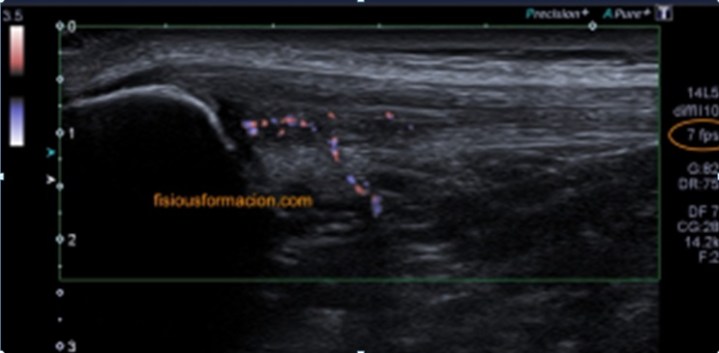

La imagen final demuestra una visión panorámica de los rectos abdominales inferiores demostrando los hallazgos que te he ido explicando durante el post. En este caso me hizo falta utilizar una función del ecógrafo muy útil que es la “función dual”, donde he dividido a pantalla en dos y he podido comparar en una misma imagen tanto a normalidad como la zona patológica, con un considerable aumento de la resolución de la imagen y un aumento en la calidad global de esta tanto en corte transverso como en longitudinal. Esta función dual permite el estudio comparativo con doppler. Muy útil, aunque el almacenamiento masivo de imagen en el pacs hace que esta función haya caído paulatinamente en desuso.

Estos hallazgos dado el contexto clínico sugieren foco de endometriosis. En este caso eran focos o implantes de endometriosis que tras la cirugía pudieron quedar diseminados por el tejido muscular.